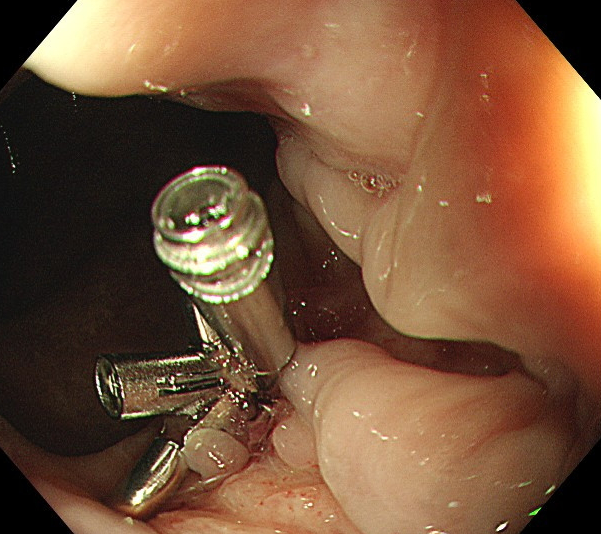

“一定是那个血痂掉了!”曹主任再次紧急予急诊肠镜检查,果不其然,肛门口的血痂已经掉了,露出一裸露的血管头,正在咕咕地冒着鲜血。曹主任立即给予内镜下止血治疗,随着几枚钛夹的置入,出血立马就止住了,立竿见影!

内镜下置入的钛夹

曹主任悬着的心终于放下了。接下来,她又仔仔细细检查了方大妈结肠的各个部位,确定没有其他的出血点,同时,她发现方大妈之前的结肠多发溃疡已经明显好转,这让她在紧张之余也增添了一分欣慰。做完肠镜夜色已深,虽然身体很疲惫,但是看到出血的病灶被成功修复,曹主任还是长长地舒了一口气。